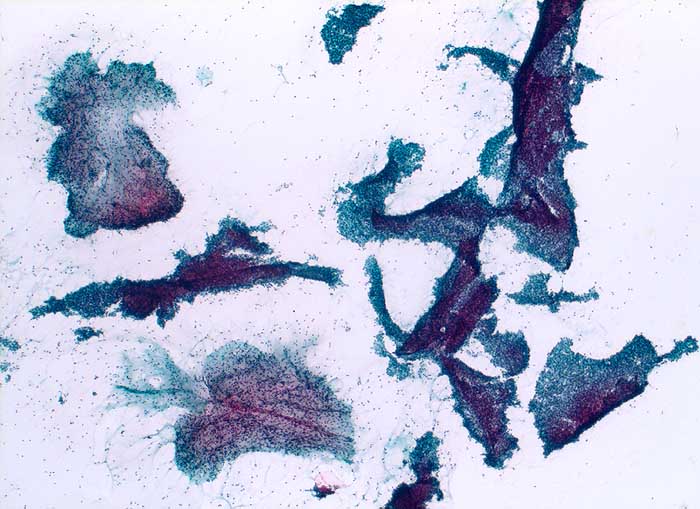

Grosse Mengen epithelialer Zellen, bipolarer Nacktkerne (Myofibroblasten und Fibrozyten) und scharf begrenzte Stromafragmente charakterisieren das Fibroadenom zytologisch. Aspirate von stark fibrosierten Fibroadenomen können auch zellarm sein. Einseitig von Epithel bedeckte Bindegewebsfragmente sprechen für ein Fibroadenom. Durch die Aspiration wird die epitheliale Innenauskleidung mit ihren Verzweigungen aus dem Gangsystem gelöst. Die Epithelverbände sind beim intrakanalikulären Fibroadenom flach und erscheinen beim perikanalikulären Fibroadenom T-, Y-, finger- oder hirschgeweihförmig. Die Kerne sind wenig grösser als die Kerne normaler duktaler Epithelien und messen meist weniger als zwei Erythrozytendurchmesser. Da es sich bei Fibroadenomen um proliferierende Läsionen handelt können die Epithelzellen Zeichen der Aktivierung zeigen in Form einer mässig ausgeprägten Pleomorphie, prominenten Nukleolen, und gelegentlichen Mitosen.

Das erste Beispiel zeigt ein intrakanalikuläres, das zweite Beispiel ein perikanalikuläres Fibroadenom mit stark verzweigten Zellverbänden. Das dritte Beispiel zeigt die Zytomorphologie eines Fibroadenoms mit stark aktivierten Zellen.